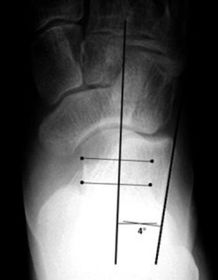

What is this angle called? Is this normal or abnormal? | AP - Talo-calcaneal angle This is normal |